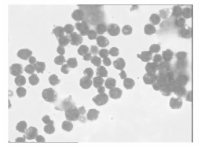

7. 腹水检查 (1)生化检查:乳酸脱氢酶2 758 U/L, 腺苷脱氨酶(ADA) 97 U/L; (2)形态学检查:外观呈黄色浑浊液体, 李凡特试验为弱阳性, 红细胞计数1 280× 106/L, 白细胞计数36 000× 106/L。将腹水离心, 取沉淀物涂片进行瑞氏染色置于油镜下观察, 查见大量异常细胞。该类细胞大小不一, 胞质量少, 胞浆呈深蓝色且有空泡, 核型不规则, 核染色质疏松分布不均, 核仁1~2个, 并且该类细胞几乎占据整张涂片, 而背景细胞极其少见, 疑似淋巴瘤样细胞; (3)免疫学检查:腹水样本经流式细胞(FCM)白血病免疫分型显示, 异常细胞占白细胞总数的97%, 异常细胞表达B系淋巴细胞抗原, 分别为HLA-DR(+)、CD10(+)、CD19(+)、FMC-7(+)、CD20(+)、CD38(+)、Lambda(+)、cCD79a(+)。